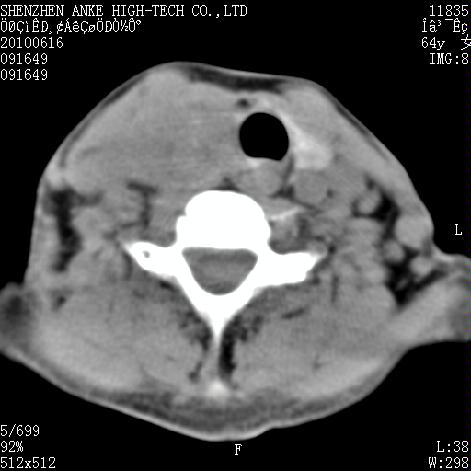

标题: CT27132:患者女,64岁,颈部及全身多处包块,现觉吞咽困难4 [打印本页]

标题: CT27132:患者女,64岁,颈部及全身多处包块,现觉吞咽困难4

右侧甲状腺占位,肿瘤可能性大,癌

右侧甲状腺癌伴淋巴结转移

右侧甲状腺占位,腺瘤可能性大